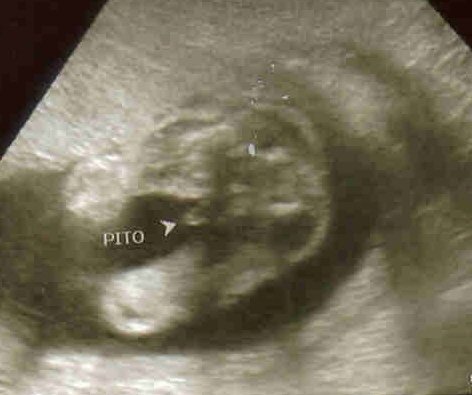

Kép A kis futyis (pito=futyi)

Rita! Nekem ugyanez van, mélyen tapad a méhlepény. Ugyanígy megijedtem, végigolvastam mindent, aztán a doki megnyugtatott. Ugyanazt mondta, mint a tied: feljebb kerül, ha nő a méhed. Addig meg ne nagyon cipekedj! Szóval nyugi. :-) Azt is mondta, hogy ez elég gyakori.

A terhesség első felében gyakran látható UH-vizsgálatkor a méhszáj területén a lepény. A terhesség előrehaladtával magasabbra kerülhet (placentamigratio).

Ilyenkor javasolt a minél több pihenés, nehéz terhet nem szabad emelni, no sex. Nem szabad méhszáj vizsgálatot sem végezni!